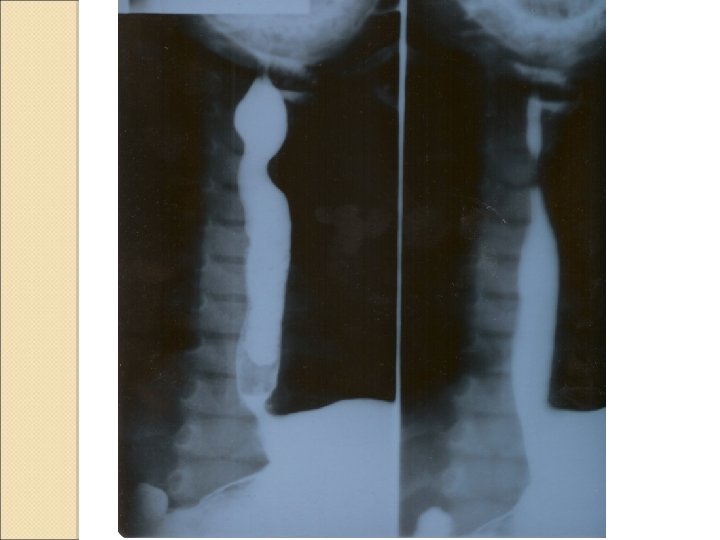

Çift aortik ark basısı

Differential diagnosis ◦ Extrinsic airway anomalies resulting in airway compression Vascular ring or sling Mediastinal lymphadenopathy Mediastinal mass/tumor ◦ Intrinsic airway anomalies Airway hemangioma Cystic adenomatoid malformation Bronchial/lung cyst Congenital lobar emphysema Aberrant tracheal bronchus Sequestration Congenital heart disease with left-to-right shunt (increased pulmonary edema)